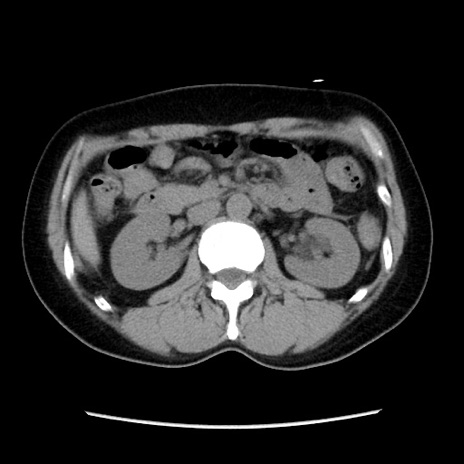

症例10(横断像)

【症例】 50歳代女性

【主訴】 腹痛

【現病歴】前日生レバーを食べた。今朝に排便あり。 昼前に突然発症の腹痛を生じ、当院救急外来を受診した。

【既往歴】 子宮筋腫にてで子宮全摘後

【身体所見】 意識清明、腹部:平坦、軟、下腹部やや左を中心に圧痛・反跳痛あり、筋性防御あり

【データ】WBC 7800、CRP 0.07